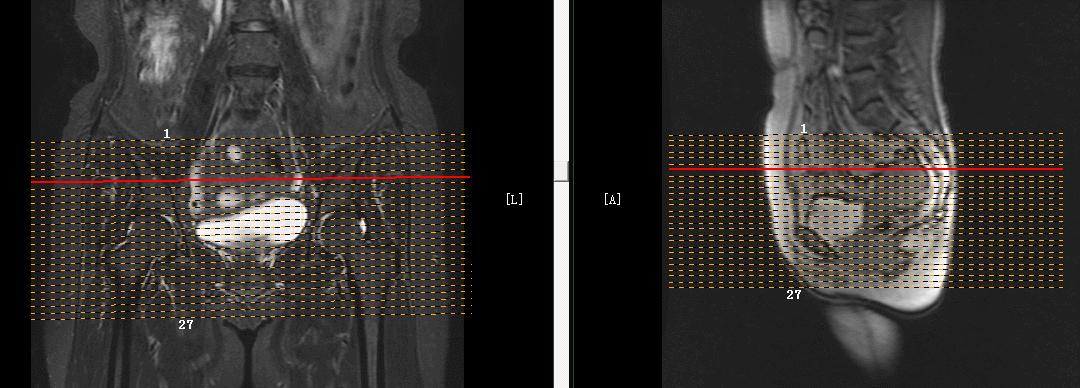

子宫MRI扫描前应先行1-2个大范围的 全盆腔 扫描序列,通常为大范围的T1WI和T2WI 压脂序列;在冠状位和矢状位上定位,按照常规的横轴位扫描即可。

行大范围扫描的目的:

1.了解盆腔内病变的大体情况。

2.观察盆腔内出血、转移、周围侵犯等情况。